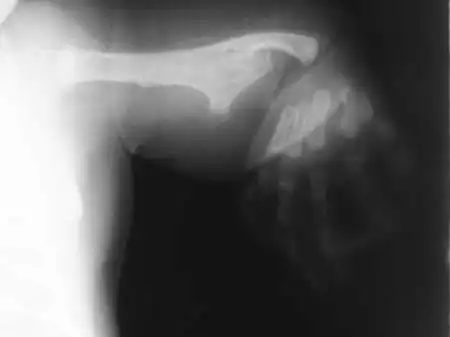

Врожденное уродство...

И, конечно же, всевозможные патологии внутренних органов...

В медицинских альбомах фотографий, составленных западными специалистами, есть младенцы, рожденные с внутренними органами вне тела и без половых органов...